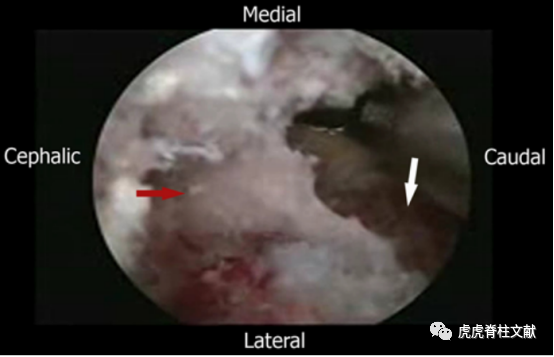

2.关节镜下磨钻清理软组织,白色箭头指示上位椎板和棘突基部,红色箭头指是椎板间隙

3.Kerrison椎板钳切除上椎板的下缘和关节突的内侧半部分;红色箭头指向上椎板,白色箭头指向关节突切除部位